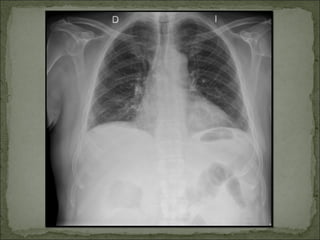

Similar    a Pielonefritis, Rx abdomen: método

evolución tórpida:           inespecífico.

DIAGNÓSTICO Similar a Pielonefritis, Rx abdomen: método evolución tórpida: inespecífico.  Tipo 1: Mortalidad 70 a Ecografía renal: gas en el 90%. parénquima renal y vías  Tipo 2: Mejor urinarias. pronóstico. TC: método de elección.